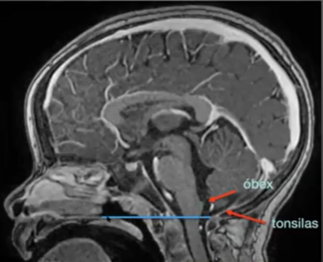

Chamberlain: Palato duro até o opistio (positivo se < 2mm abaixo)

Note que no normal o óbex (marca o começo do canal medular central) tem que estar na linha ou acima dela (marca também o grácil e cuneiforme). A tonsila também acima e o dontoide abaixo (se estiver acima vai chamar de invaginação basilar)

Tipo 1: Apenas a tonsila hernia pelo forame magno

Tipo 1,5: Tonsila e o tronco cerebral (o óbex fica abaixo da linha de chamberlain)

Imagem Chiati tipo 1.5

Tipo 1.5 = Além da tonsila, desce o tronco cerebral (obex abaixo da linha)

Costuma ser mais grave e mais resistente que a tipo I